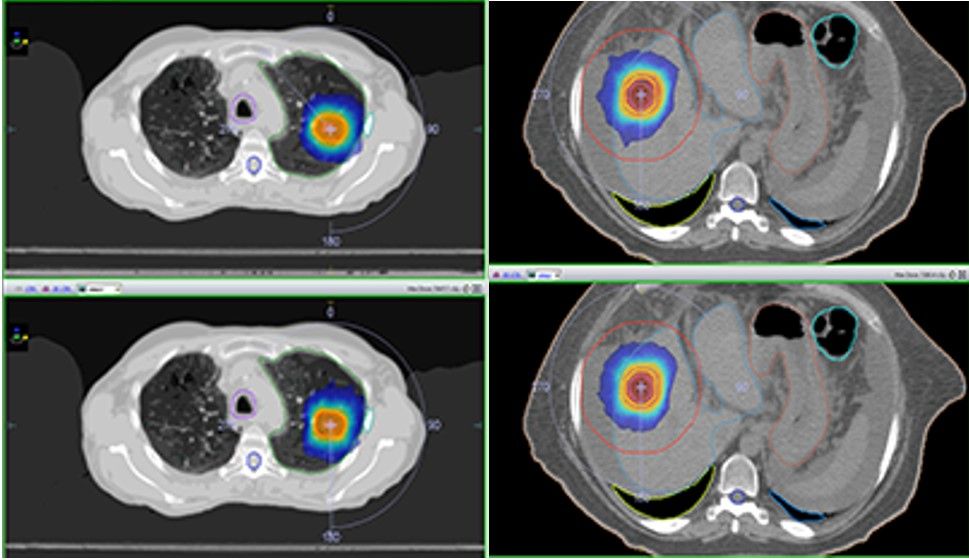

图显示了优化后的DCAT(上)和VMAT(下)等剂量分布之间的比较,显示了可比较的计划质量(图1)。

图1

图2 &3:肺部SBRT病例(左)和肝脏SBRT病例(右)的优化DCAT(上)和VMAT(下)等剂量分布和剂量体积直方图(VMAT:实线,DCAT:虚线)的比较。